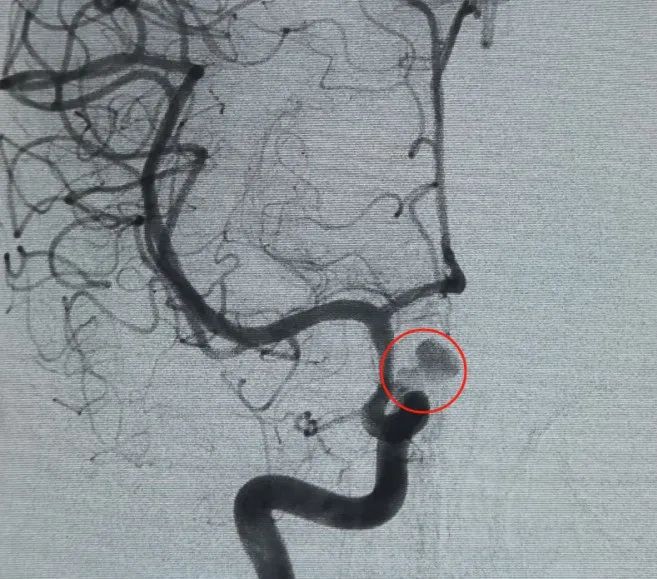

Tanı: sol iç karotis arter c6 segment oftalmik arter anevrizma

Femoral arter delinmesi ve daha yoğun bir şekilde vasküler erişim kuruldu®6mm × 20 cm 3d bobin ilk olarak bir sepet oluşturmak, istikrarlı duvar ataması elde etmek ve güvenli accus. lar destek sağlamak için yerleştirildi. Bu, daha yoğun bir şekilde yerleştirilmesiyle takip edildi®Lobulated kızı kesesi içinde kan akışını bozmak için 6mm × 15 cm 3d bobin.

Bir perfiller®3mm × 6 cm genişletilebilir bobin ve bir perfiller®3mm × 2 cm genişletilebilir bobin daha sonra boyun tıkanıklığını tamamlamak için yerleştirildi. Daha sonra bir nuva®Akış değiştirici (TJED-D-5.0-16) anevrizma boynu boyunca teslim edildi ve dağıtıldı. Anteroposterior ve yanal görüşlerde takip anjiyografisi, işaretlenmiş kontrast durgunluğu ile mükemmel kapsama, iyi duvar atama ve net radiopacity onayladı.